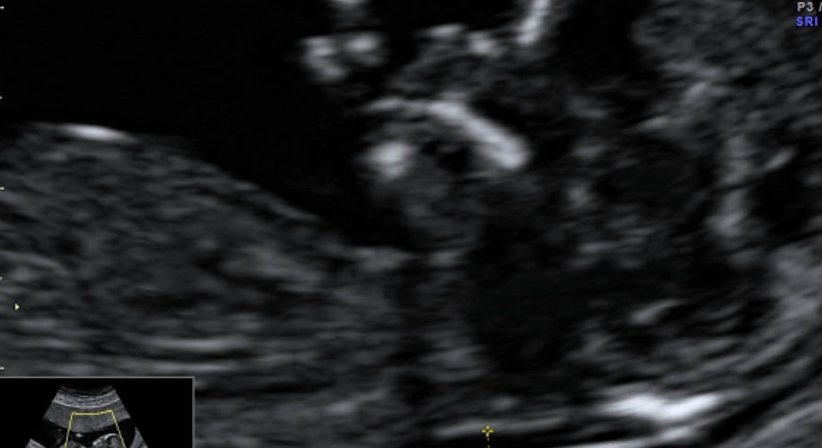

Bei der NT wird die Dicke der Falte im Bereich des Nackens gemessen, diese sollte unter 3mm sein.

Diese Untersuchung ist stark von der Lage des Babys abhängig, erfordert daher viel Geduld und Können des Untersuchers. Die Nackenfaltenmessung darf nur durch zertifizierte Untersucher (jährliche Re-Zertifizierung notwendig!) durchgeführt werden.

Durchführung zwischen 11. und 14. SSW (45 bis 85mm SSL), zu diesem Zeitpunkt mache ich auch immer die erste MKP-Blutuntersuchung und ein Infektionsscreening zur Vermeidung von Frühgeburten